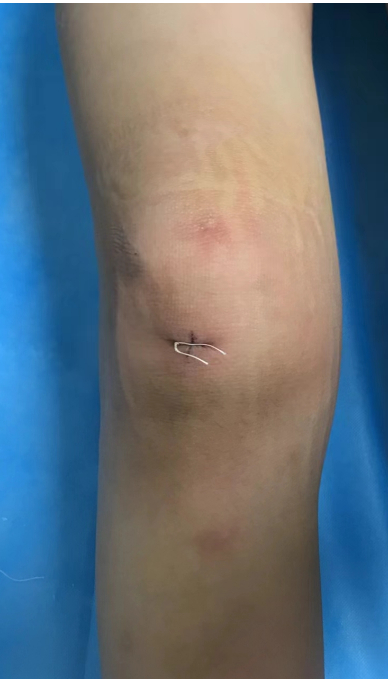

5月17日,骨科刘飞副主任医师带领侯华成医师等团队成员为小鱼实施了手术。仅在膝关节前后开了两个小孔,将关节镜从前端进入,穿过髌骨、前后交叉韧带等,避开重要神经和血管,准确到达内侧半月板后方病变处,再将手术刨刀从关节后伸入囊肿,在3倍放大的数字影像下,从囊肿内部清除囊壁,同时切除单向瓣膜。大约半小时,手术就完成了。由于创伤小,术后第二天小鱼就可以下床活动了。